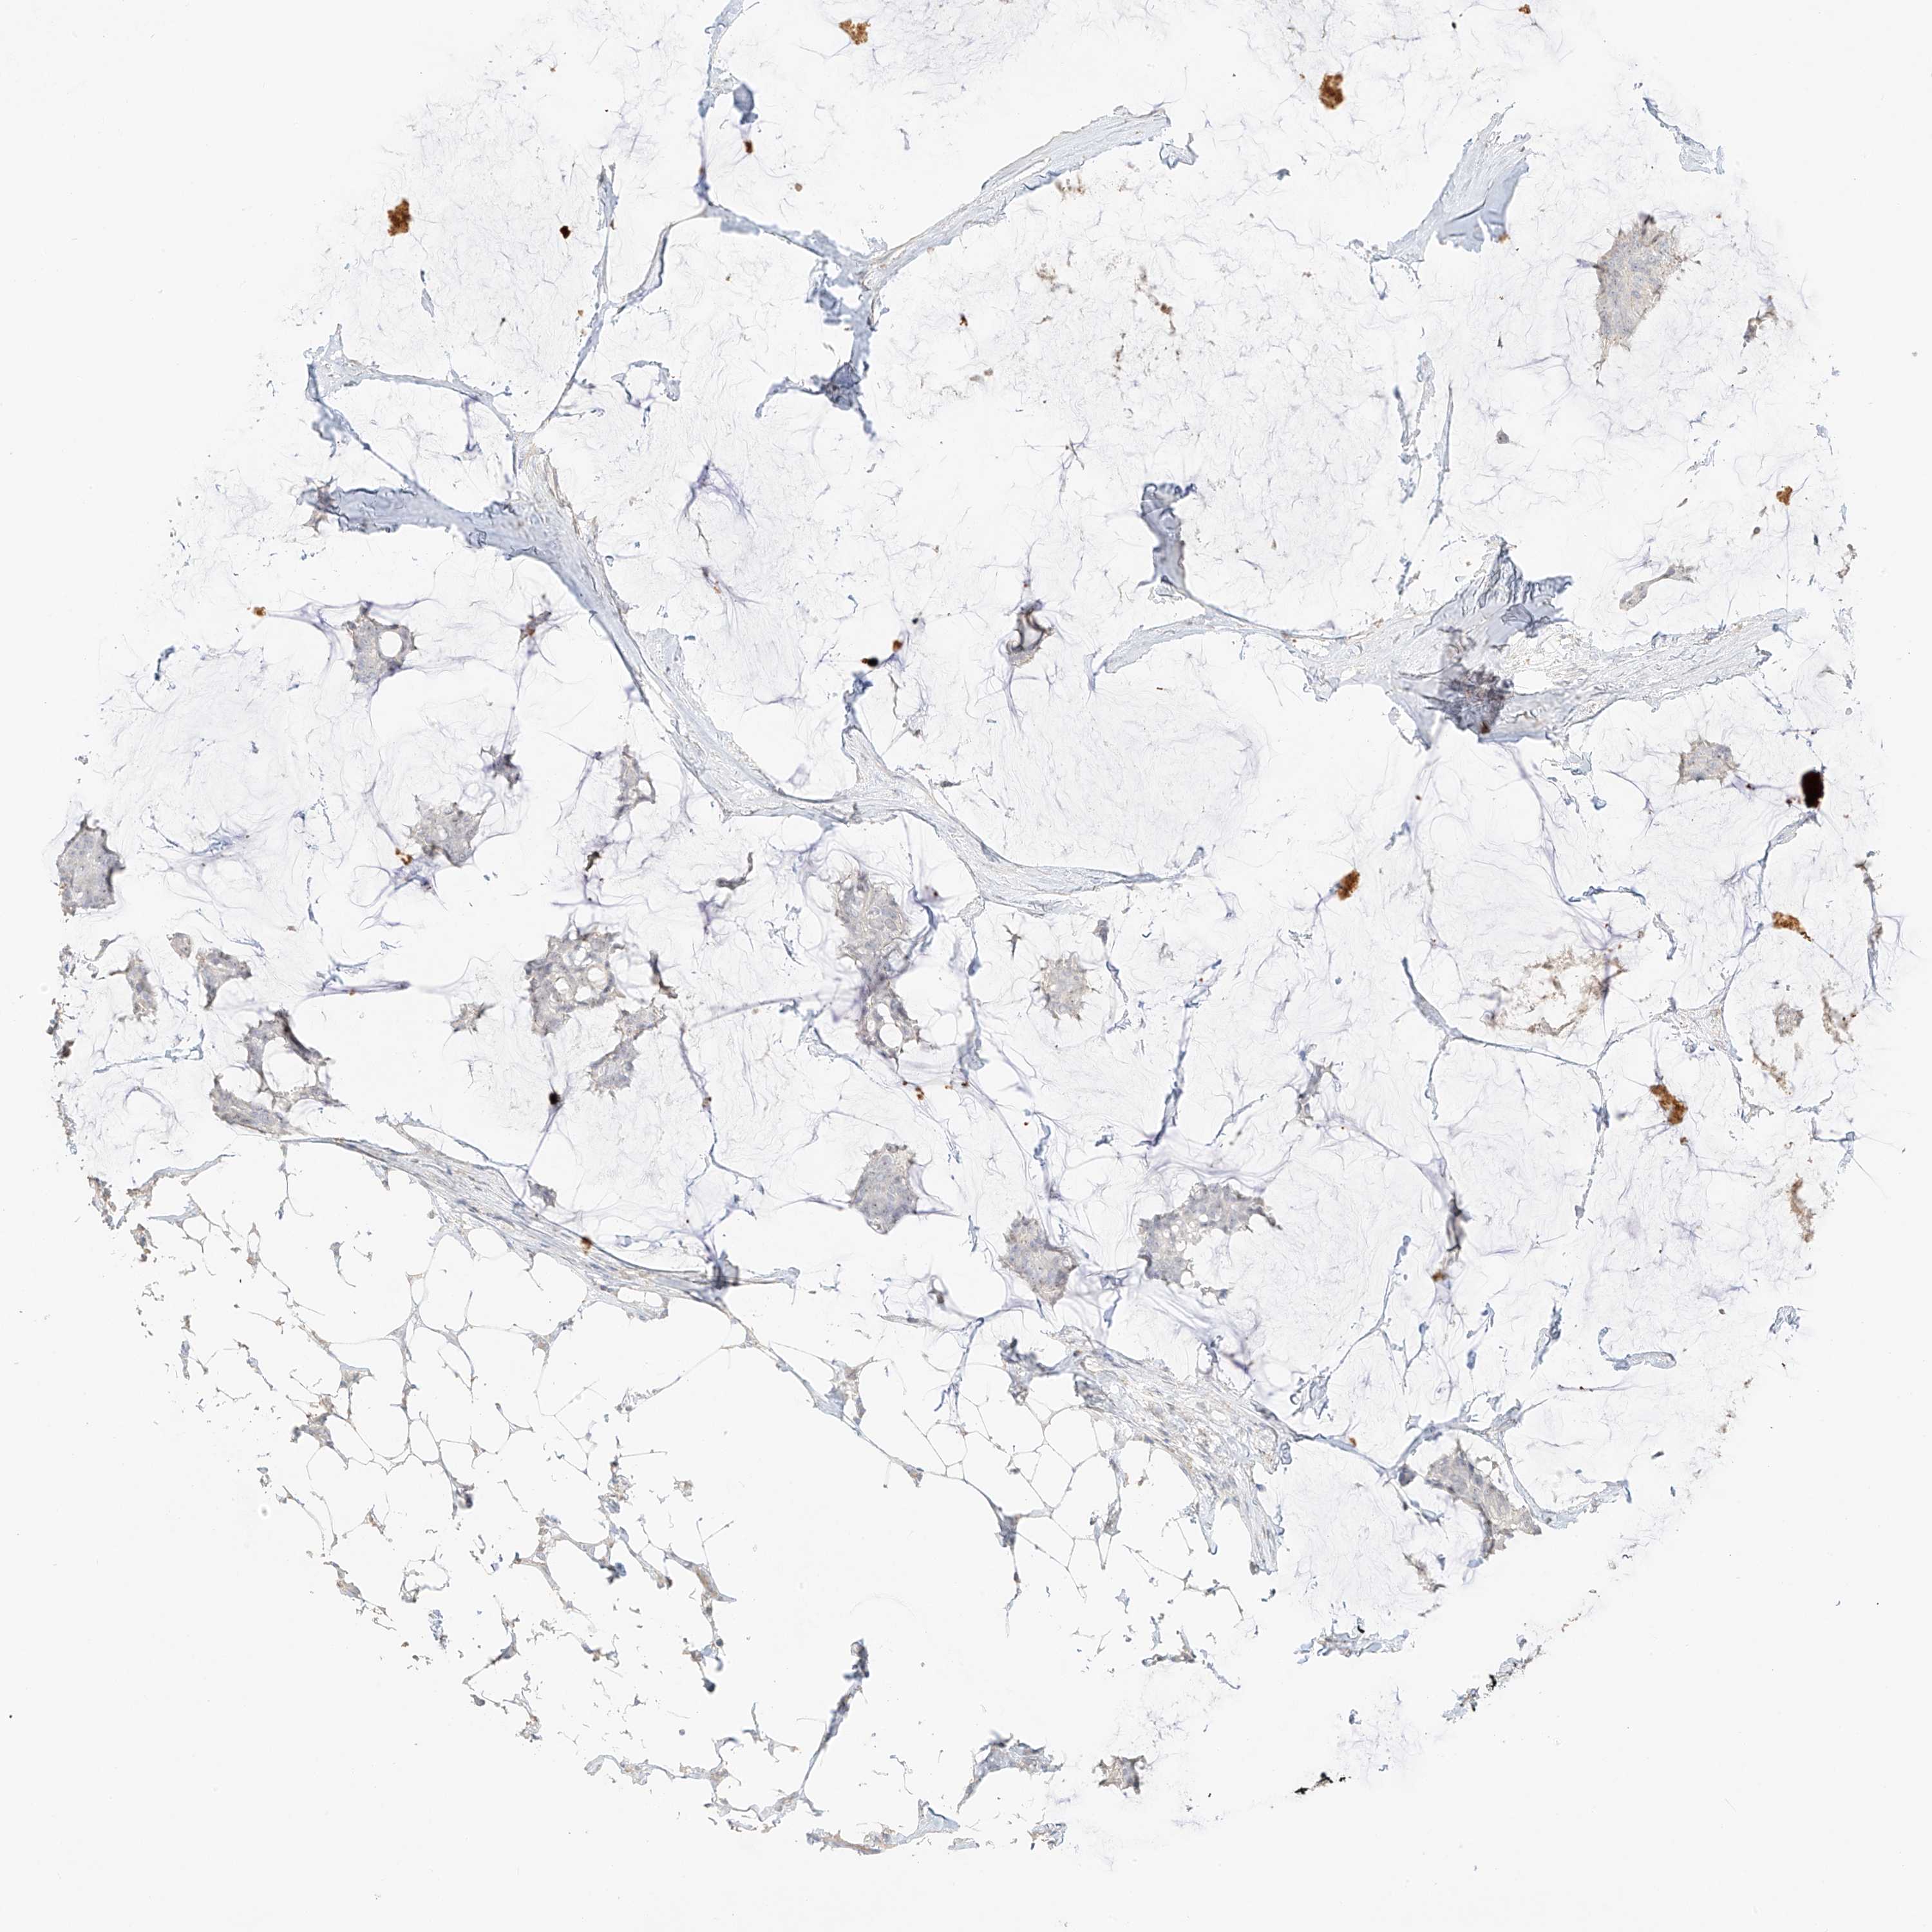

CANCER BREAST CANCER Show tissue menu

BRCA TCGA BRCA VALIDATION PROTEIN EXPRESSION